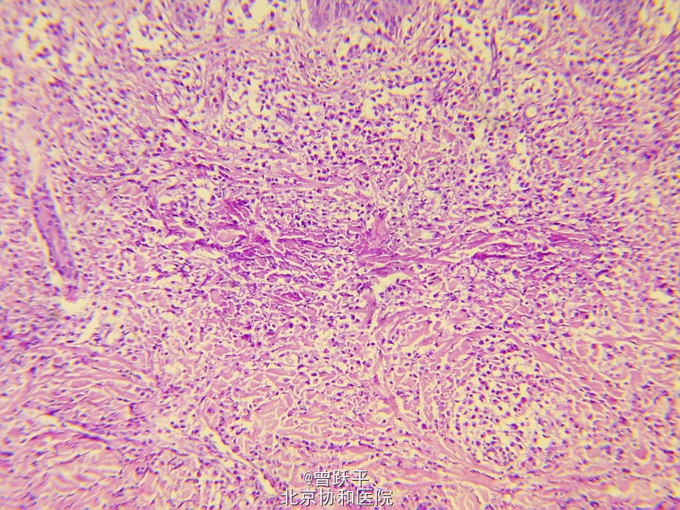

患儿女,5个半月。 因右手背皮肤结节、水疱、血疱,伴全身反复出现红斑、风团5个半月来我院就诊。 患儿出生时,右手小指掌指关节伸侧有一绿豆大丘疹,摩擦后肿大,表面起水疱、大疱或血疱,皮损渐增大。 患儿常出现全身阵发性红斑、风团和面色苍白,持续约数小时至数天后缓慢消退。 个人史:患儿系第一胎第一产,足月顺产。 家族中无类似患者。

查体:一般情况良好。系统检查无异常。全身浅表淋巴结未触及。 右手小指掌指关节伸侧可见一1.4cm×2.5cm棕红色结节,界清,橡皮样硬度。 躯干、四肢散在分布许多大小和形态不一的红斑和风团

单发性肥大细胞瘤 口服氯苯那敏2mg/d,红斑和风团明显减少,此后右手背皮损逐渐变小。